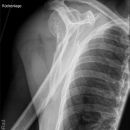

Knöcherner Supraspinatussehnenausriss